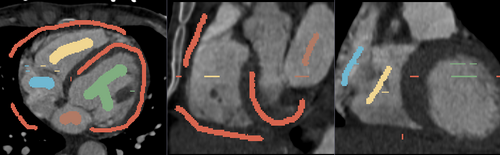

The module supports multi-label segmentations. Two examples are shown below.

• Heart chamber segmentation

FGC Heart Seed.png

1) Seed image

FGC Heart Seg.png

2) Segmentation results